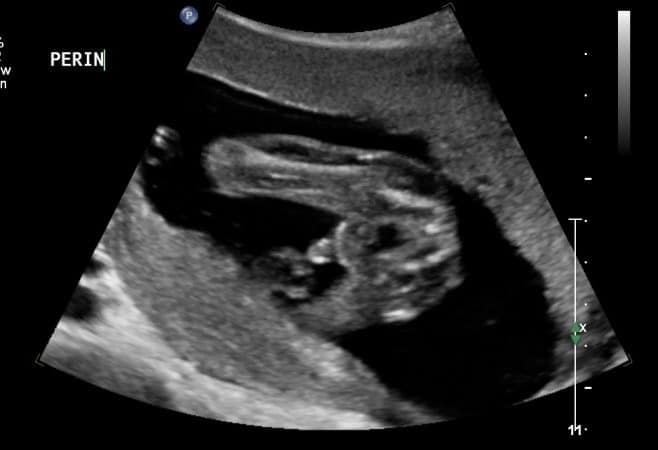

Anomaly/Detailed or morphological Ultrasound

(Please not this is not a 4D scan but a detailed 2D scan)

Preferably done at 18-24 weeks, but can be done later if the gestation was missed.

Heart

Feet

Hand

A detailed ultrasound scan that looks at your baby’s body and organs but also observes the position of the placenta, the umbilical cord, the amniotic fluid.

We will check to see if your baby has any abnormalities in their growth or development, including in their brain, face, heart, spine, stomach, kidneys bladder and limbs. Some of the abnormalities we aim to exclude are a cleft lip, spina bifida, a “hole” in the fetal heart, club feet ect.

This type of scan is very important check that your baby is healthy. I value this scan the most important ultrasound in your pregnancy.